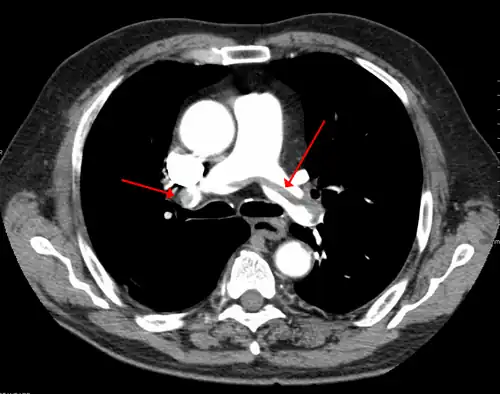

A CT image with red arrows indicating PE (grey) in the pulmonary arteries (white)

-

A pulmonary embolism (PE) occurs when a blood clot from a deep vein (a DVT) detaches from a vein (embolizes), travels through the right side of the heart, and becomes lodged as an embolus in a pulmonary artery that supplies deoxygenated blood to the lungs for oxygenation.[28] Up to one-fourth of PE cases are thought to result in sudden death.[12] When not fatal, PE can cause symptoms such as sudden onset shortness of breath or chest pain, coughing up blood (hemoptysis), and fainting (syncope).[29][30] The chest pain can be pleuritic (worsened by deep breaths)[29] and can vary based upon where the embolus is lodged in the lungs. An estimated 30–50% of those with PE have detectable DVT by compression ultrasound.[30]